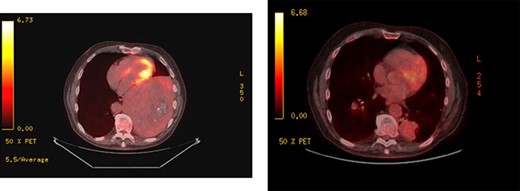

Upon re-presentation in 2019, workup included brain magnetic resonance imaging (MRI), positron emission tomography (PET) scan and re-biopsy. Brain imaging revealed a 6 mm solitary right parietal brain metastasis (Fig. 3). On PET scan, the tumour exhibited mild FDG uptake, with the SUV max of 2.9 (Fig. 4). There was no evidence of nodal or distant metastatic disease. Biopsy again was consistent with SFT. The patient was reviewed at Multidisciplinary Thoracic Tumour Board Rounds. Considering the large size and compressive effects of the pleural-based tumour, combined with the small size and asymptomatic nature of the brain lesion, it was determined that the optimal approach would be surgical resection of the left-sided pleural SFT and active surveillance of the brain metastasis. The patient underwent complete en bloc resection of the tumour via left thoracotomy including the eighth rib, partial pleurectomy and a left lower lobe wedge resection to achieve an R0 resection (Fig. 5).

PET scans; large left-sided pleural-based tumour exhibits mild FDG uptake, with the SUV max of 2.9 (left); recurrent disease at the pulmonary resection margin along with contralateral pulmonary metastases demonstrated (right).

The patient was followed closely with surveillance scans every 3 months. One year later, the patient regained 95% of his neurologic function and there was no evidence of further brain lesions; however, at that time, recurrent disease was detected at the pulmonary resection margin along with bilateral pulmonary nodules, liver and splenic metastases. The patient was treated with radiation to the recurrence at the pulmonary resection margin and initially palliative chemotherapy with Doxorubicin and Dacarbazine and was later started on Sunitinib.